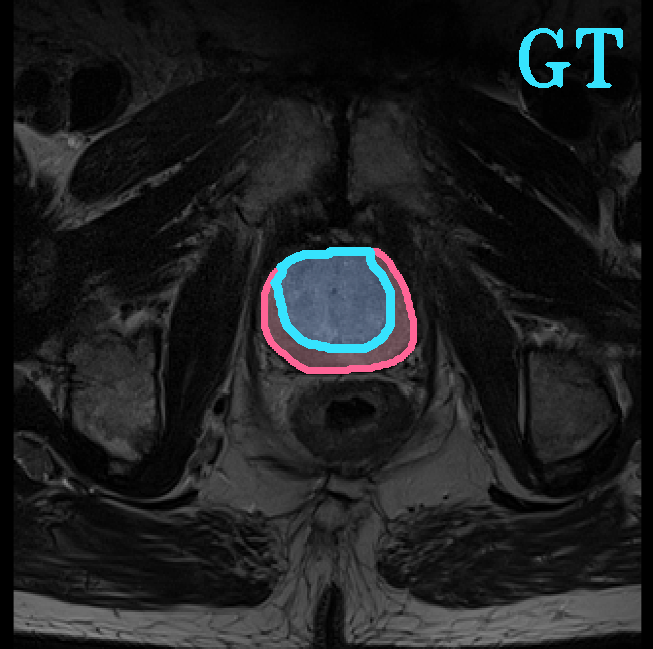

TransFuse is evaluated on both 2D and 3D datasets to demonstrate the effectiveness. As different medical image segmentation tasks serve different diagnosis or operative purposes, we follow the commonly used evaluation metrics for each of the segmentation tasks to quantitatively analyze the results. Selected visualization results of TransFuse-S are shown in Fig. 2.

Results of Prostate Segmentation. We compare TransFuse-S with nnU-Net [12], which ranked 1st in the prostate segmentation challenge [22]. We follow the same preprocessing, training as well as evaluation schemes of the publicly available nnU-Net framework333https://github.com/MIC-DKFZ/nnUNet and report the 5-fold cross validation results in Tab. 6. We can find that TransFuse-S surpasses nnUNet-2d by a large margin (+4.2%) in terms of the mean dice score. Compared to nnUNet-3d, TransFuse-S not only achieves better performance, but also reduces the number of parameters by 41% and increases the throughput by 50% (on GTX1080).

| Prostate Segmentation | |||

|

|

|

|